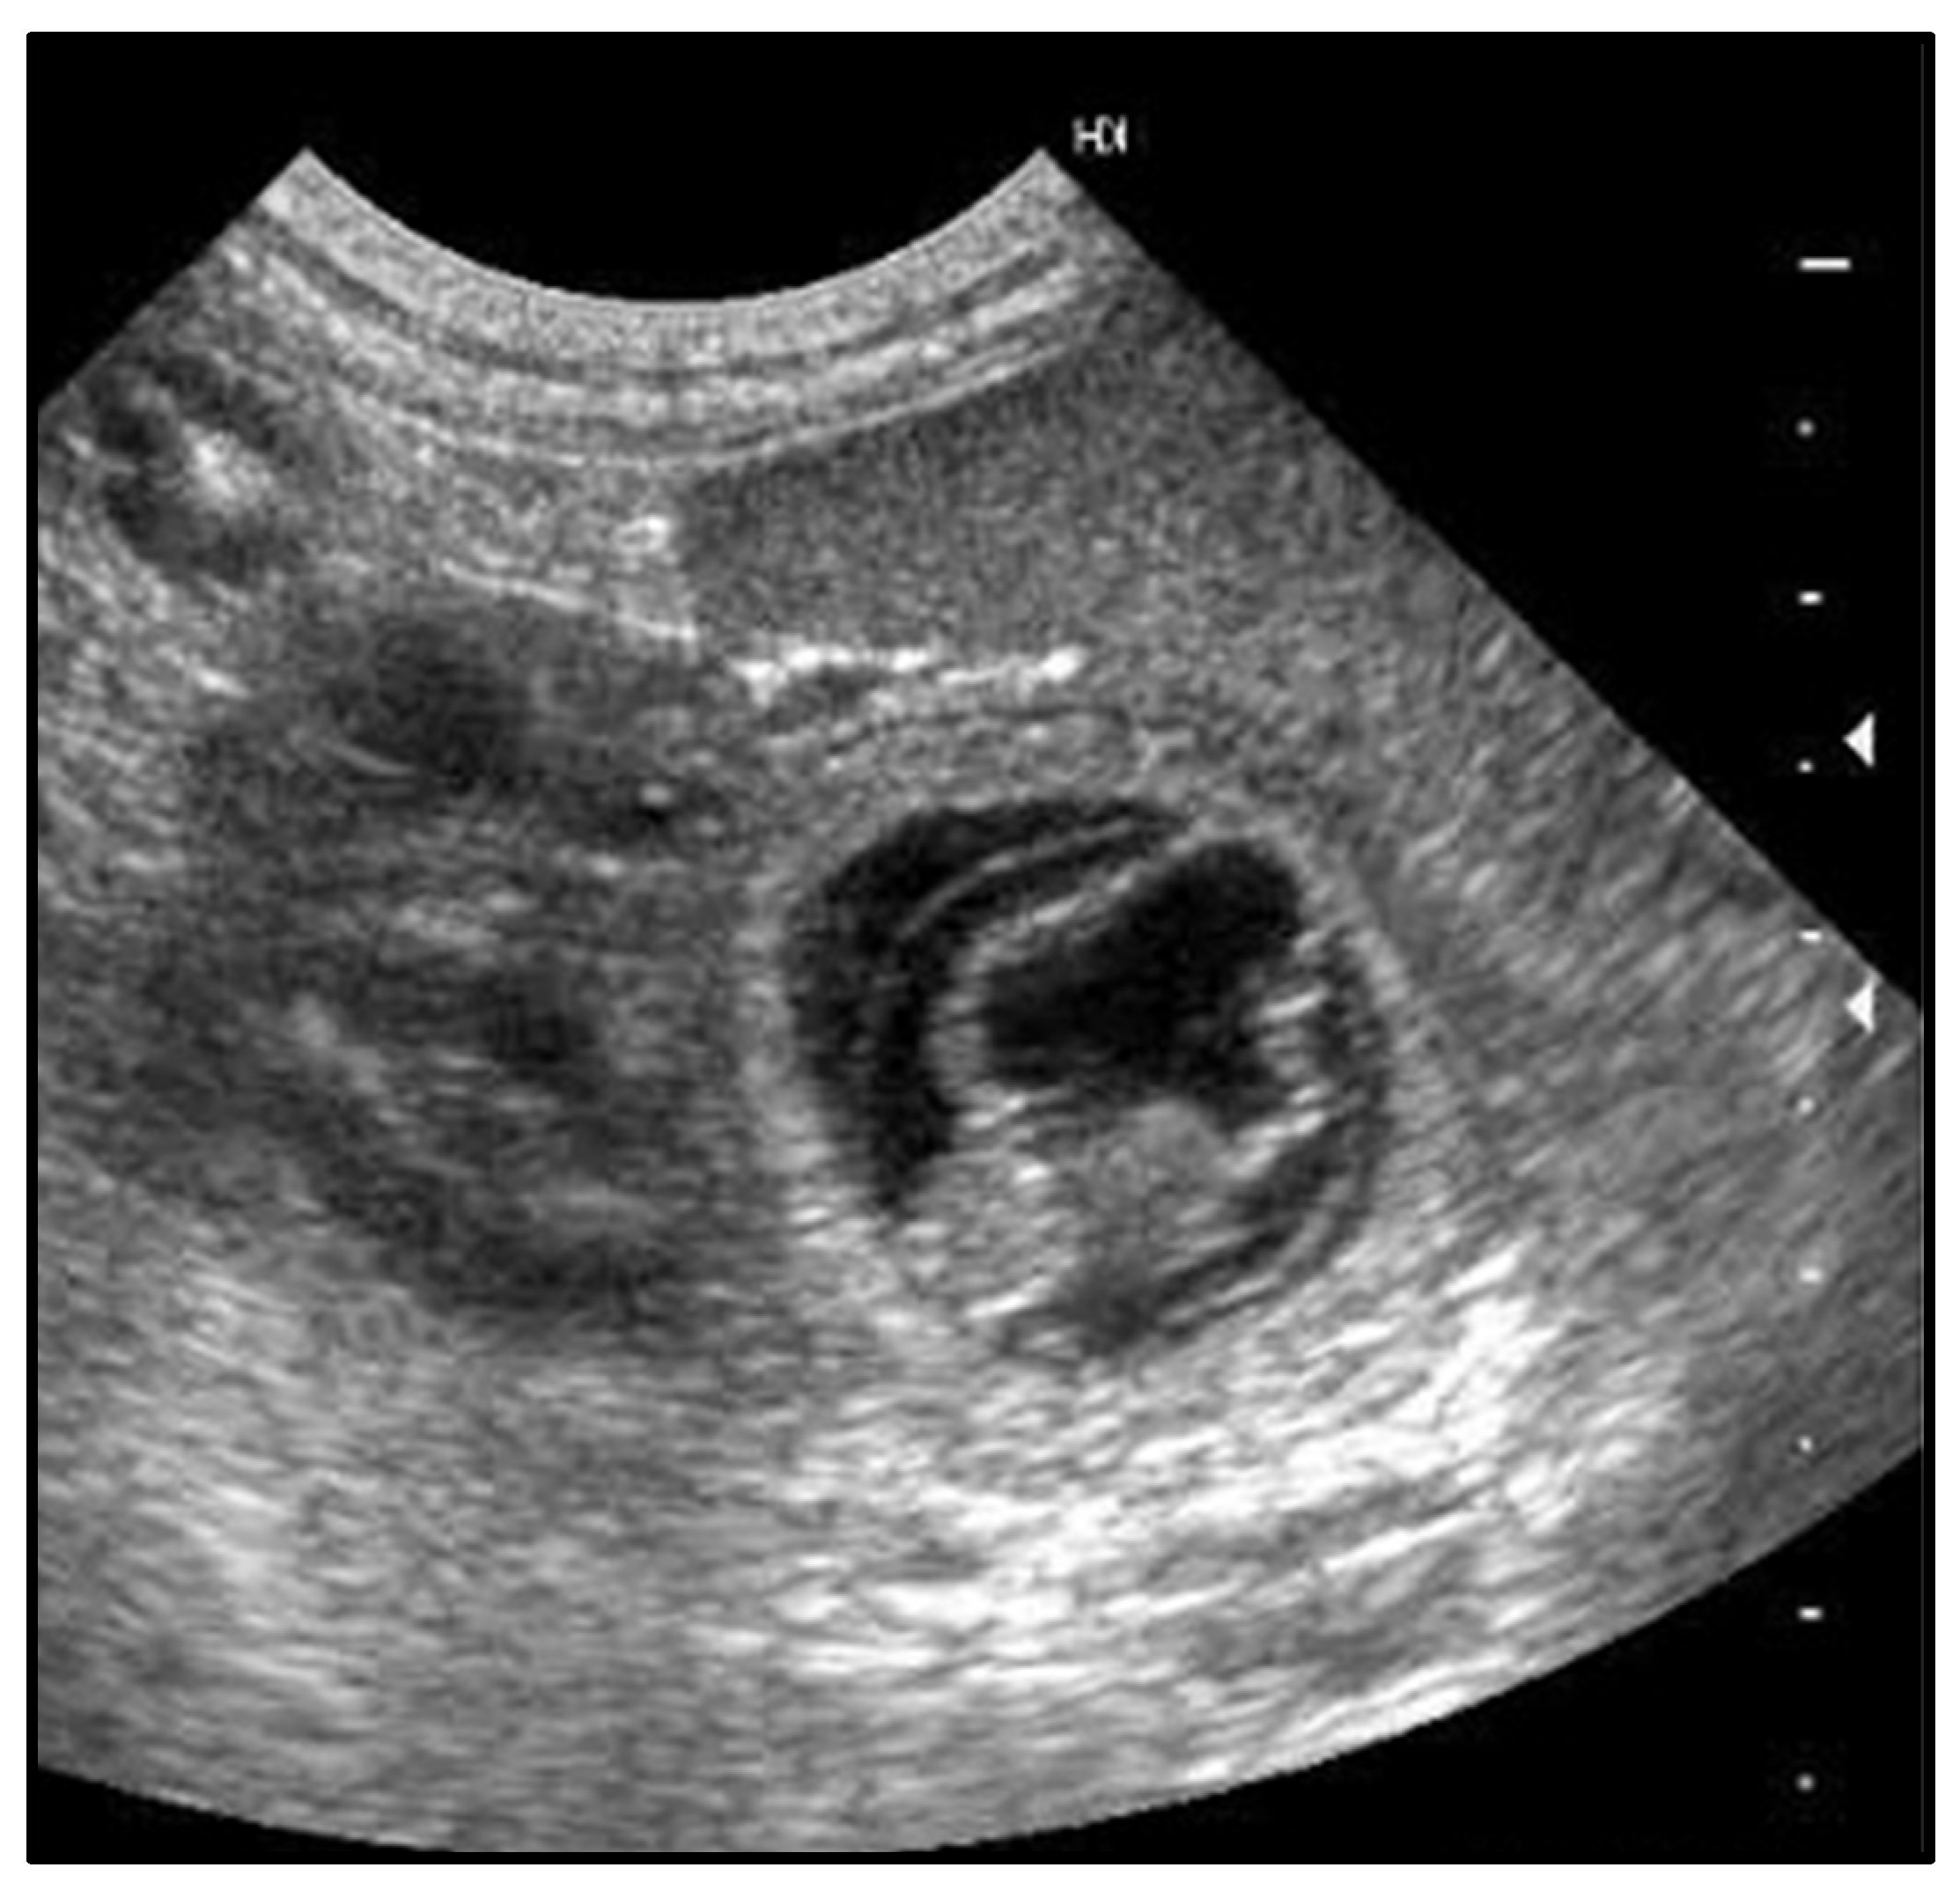

The present study evaluated the efficacy of human chorionic gonadotropin (hCG)-induced ovulation in Maine Coon queens under subtropical conditions, with catteries managed outdoors or indoors under controlled photoperiods. Seven queens in proestrus or estrus were selected based on vaginal cytology and received a single intramuscular injection of 100 IU hCG to induce ovulation. Serum progesterone levels were measured 24 hours post-treatment, and fertile toms were introduced for mating. All queens ovulated, became pregnant, and delivered within a 4-day window, with a mean gestation length of 67.9 ± 2.1 days. The mean litter size was 6.2 ± 3.2 kittens, significantly larger than historical records for the cattery (p ≤ 0.05), while neonatal mortality at birth was low (4.5%). These outcomes indicate that the applied protocol reliably induces ovulation, enhances fertility, and improves perinatal survival. The study also highlights breed-specific reproductive traits of Maine Coons, including late sexual maturity, large litter size, and susceptibility to spontaneous ovulation. Exogenous hCG administration was well tolerated, with no adverse effects observed. Overall, the findings support the use of hCG-induced ovulation as a practical and effective strategy for reproductive management in Maine Coon breeding programs, particularly under controlled environmental conditions, enabling optimization of litter timing, size, and neonatal survival.

- Zambelli, D.; Castagnetti, C.; Belluzzi, S.; Paladini, C. Correlation between Fetal Age and Ultrasonographic Measurements during the Second Half of Pregnancy in Domestic Cats (Felis Catus). Theriogenology 2004, 62, 1430–1437. [Google Scholar] [CrossRef]

- Keiser, R.; Reichler, I.; Balogh, O. Are Foetal Ultrasonographic and Maternal Blood Progesterone Measurements near Parturition Reliable Predictors of the Time of Birth in the Domestic Cat? Reprod Domestic Animals 2017, 52, 487–494. [Google Scholar] [CrossRef]